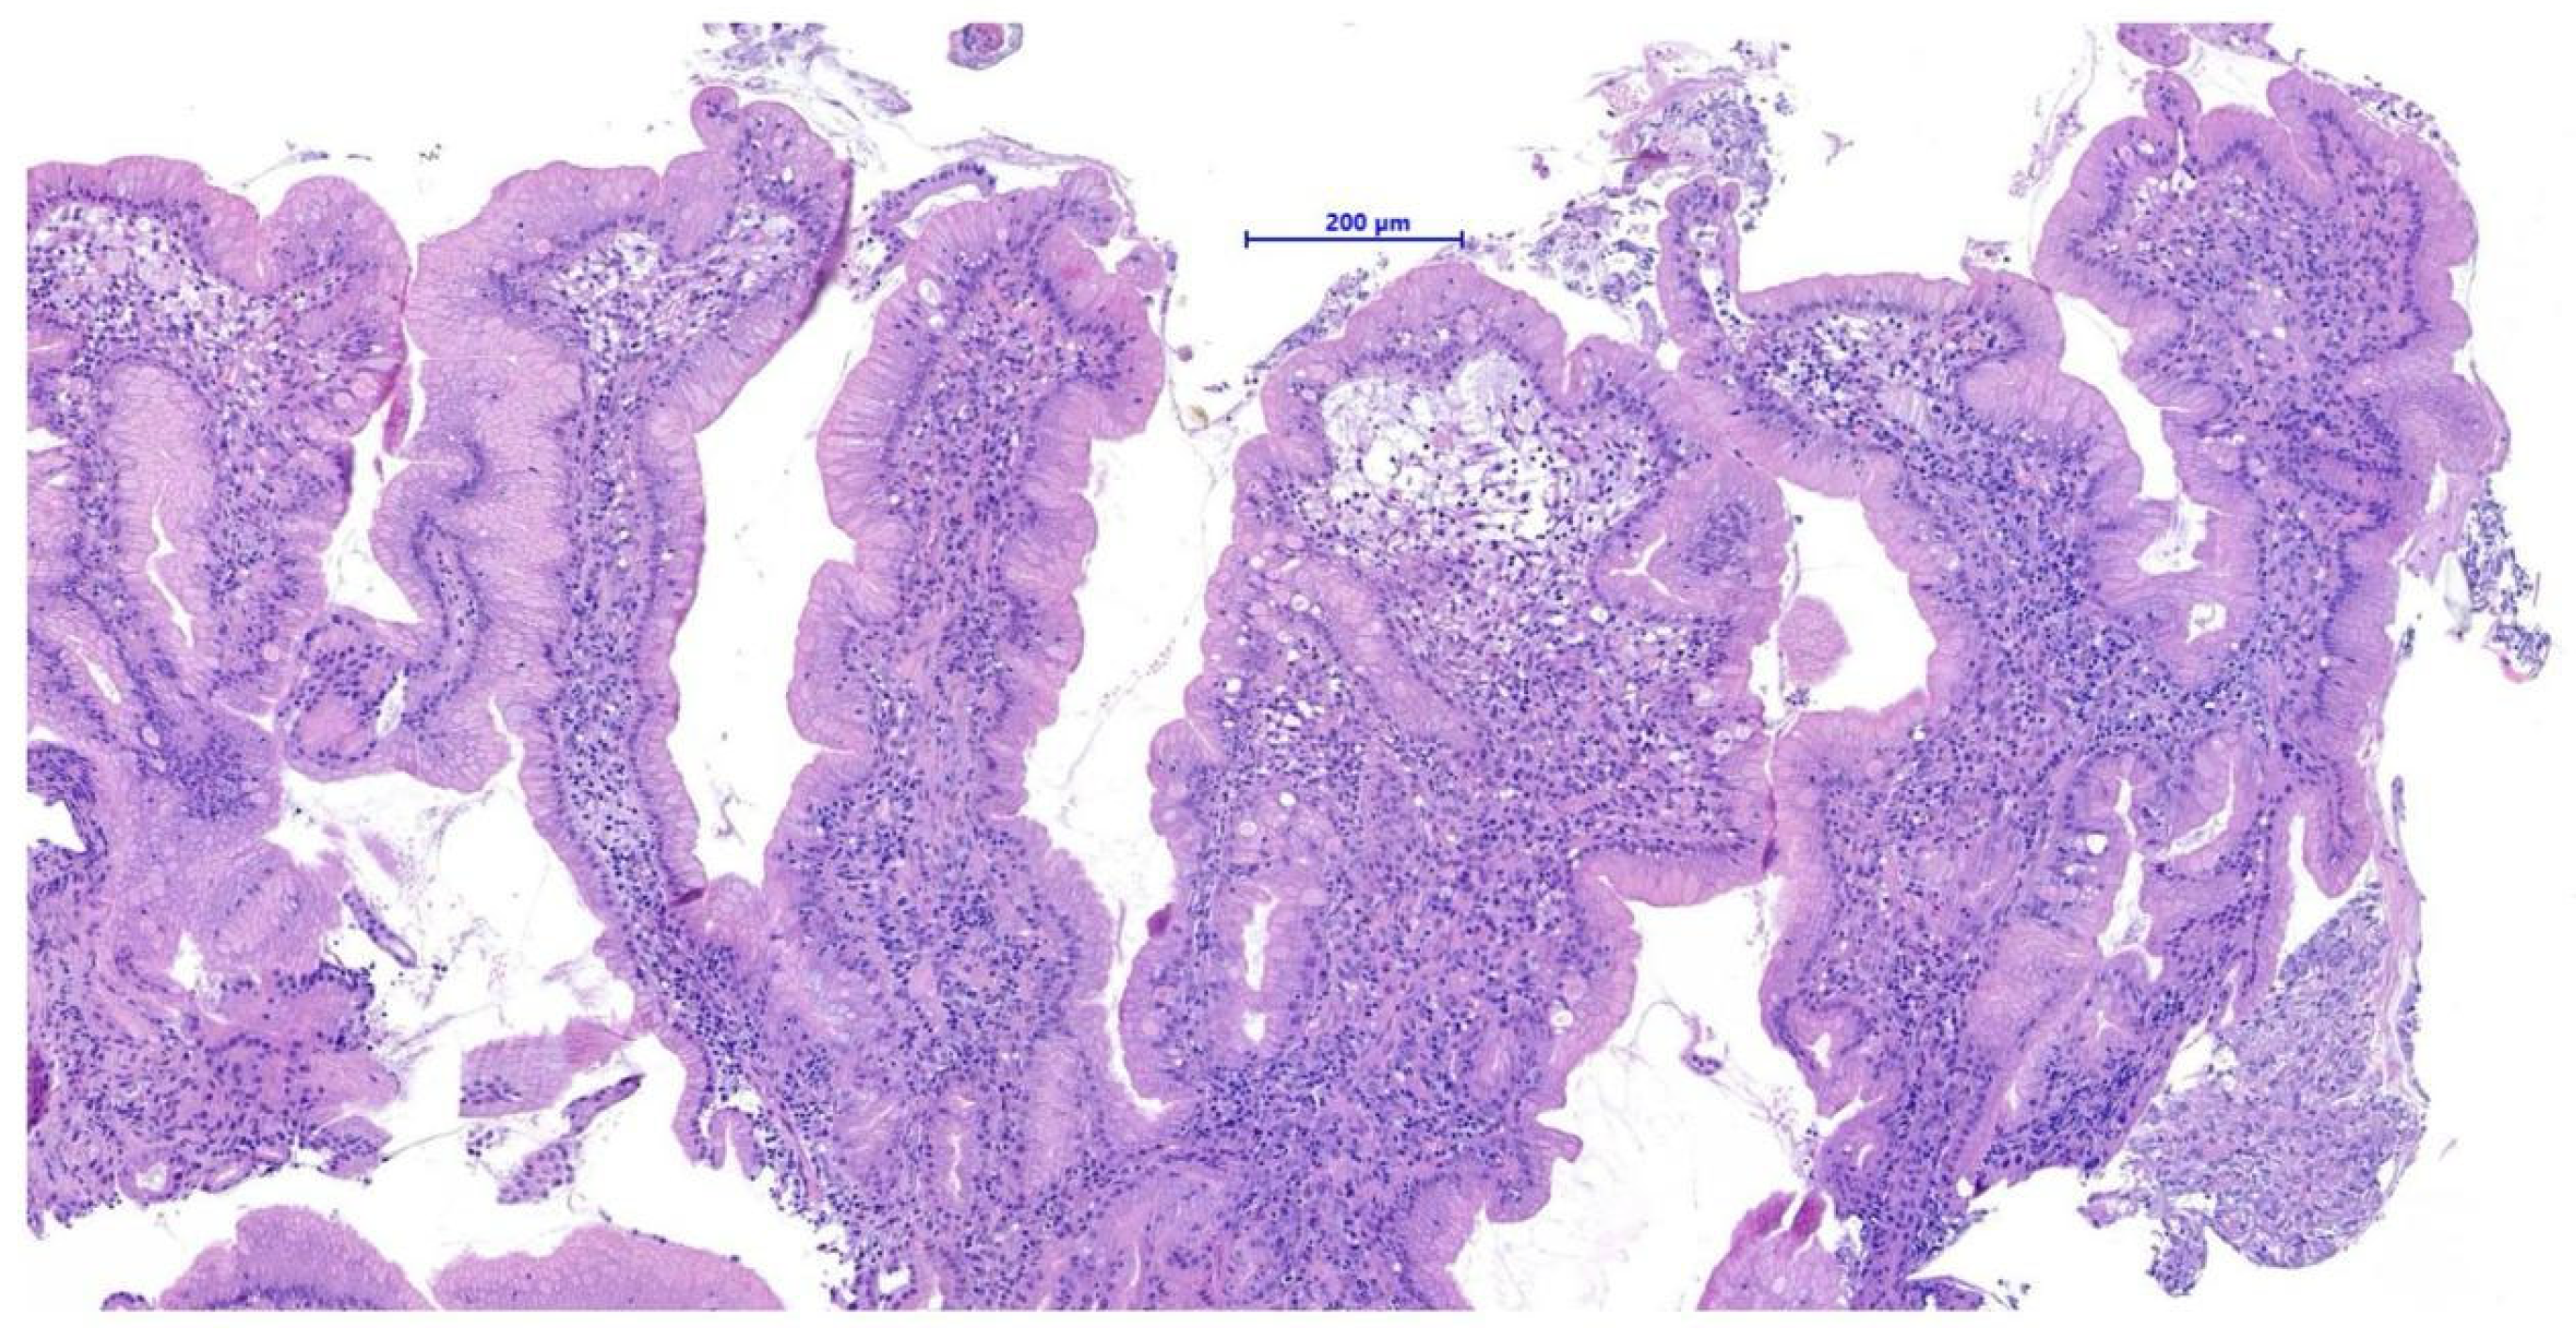

Endoscopic biopsies collected from this area revealed coalescent villi with thickened and edematous apices, without damage to the surface epithelium. Occasional glandular dilatation was observed, indicating mild epithelial injury. No lymphatic vessel dilation was present. Mucosal fibroplasia was mild. The number of intraepithelial lymphocytes was within normal limits, while the lamina propria showed moderate infiltration of lymphocytes and plasma cells, along with a mild increase in neutrophils. These findings were interpreted as consistent with a moderate chronic- active lymphoplasmacytic and neutrophilic enteritis with mild fibroplasia, suggestive of a post- inflammatory reparative phase, consistent with the resolution of previously diagnosed FGESF (Figure 4).

Histopathological evaluation of both the initial duodenal mass and the follow-up biopsies showed no lymphoid atypia or features consistent with lymphoma.

Figure 4. Histological section: moderate chronic-active lymphoplasmacytic and neutrophilic enteritis with fibroplasia H&E, 200×, scale bar = 200 µm.